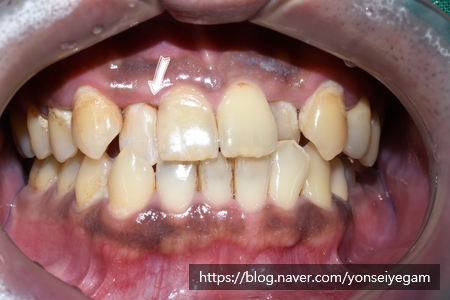

심한 위쪽 앞니 4개 심한 충치 치료만 진행한 후의 사진입니다.

앞에서 보이던 충치(화살표부분)도 레진 치료로 자연스럽게 레진 충치치료가 된 상태입니다.

앞니 외의 다른 치아들도 치료가 필요한 상태입니다.

뿐만 아니라 스케일링을 며칠 전에 한 상태였으나

양치질이 잘 되지 않아 치태가 금방 쌓여있어

치아 삐뚤어 힘들겠지만 환자 본인의 올바른 양치질 등 추후 관리도 필요한 모습입니다.